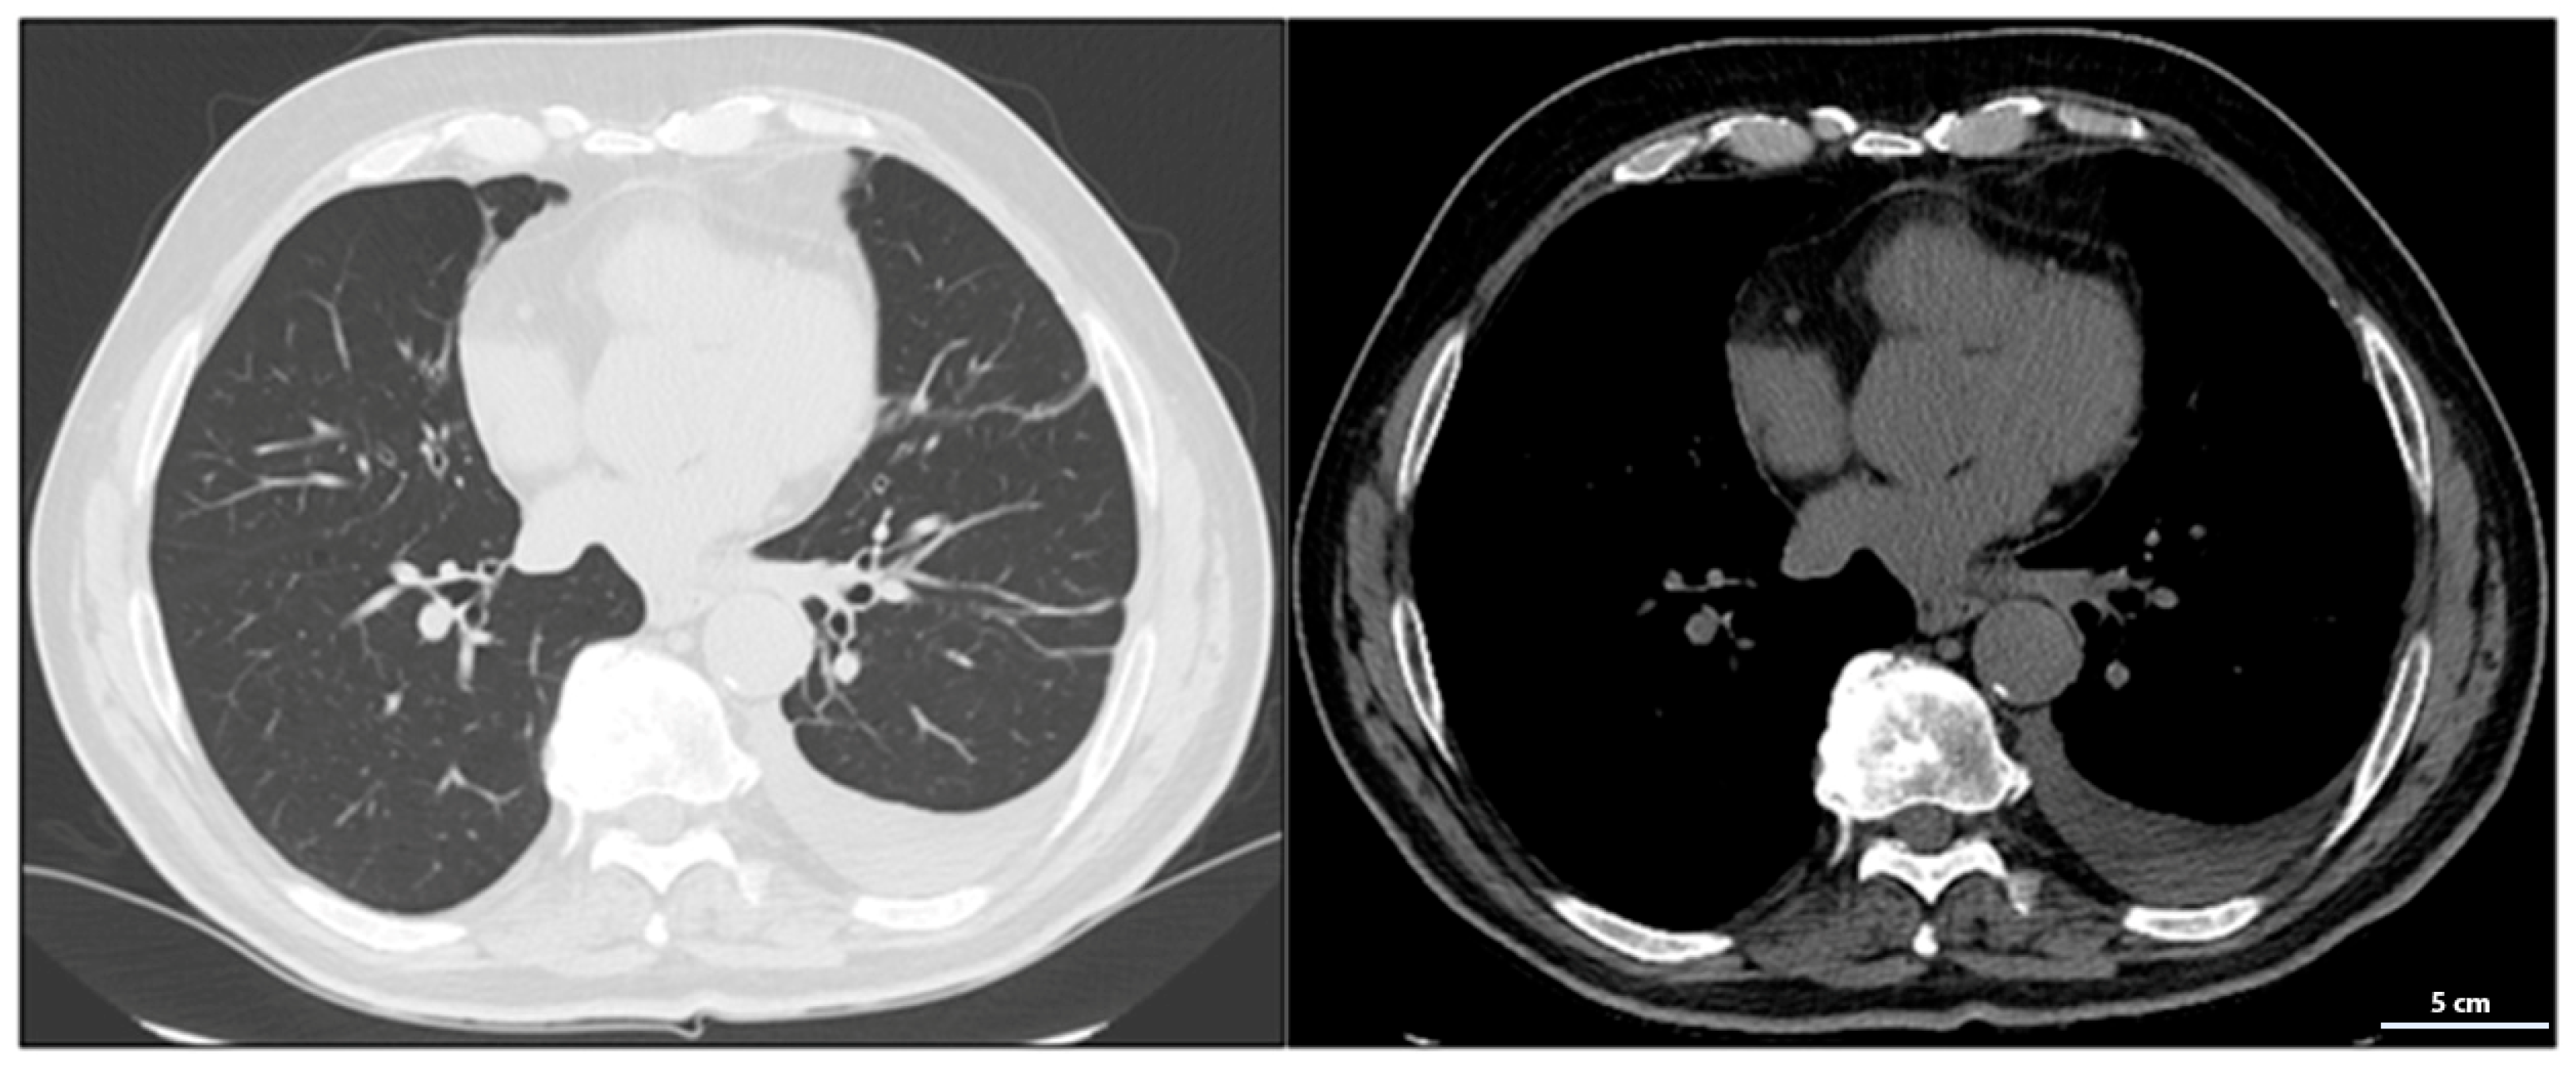

During treatment, the patient underwent serial total-body CT scans to assess the response to therapy (Table 1). The first follow-up CT, performed in June 2023, detected a left postero-basal pleural effusion, likely related to the prior wedge resection surgery (Figure 4). To manage this complication, dexamethasone 8 mg daily was administered for one week. Although the dexamethasone dose was higher than the generally recommended threshold for minimizing immunosuppression (equivalent to <10 mg prednisone/day), it was prescribed for a short duration to achieve rapid symptom control, balancing the therapeutic benefit against potential impact on atezolizumab efficacy. As is well-known, corticosteroid use in such cases must be limited due to concurrent immunotherapy with atezolizumab. While corticosteroids effectively reduce inflammation and pleural effusion, their immunosuppressive effects can attenuate the efficacy of immune checkpoints inhibitors. High doses or prolonged corticosteroid use may compromise atezolizumab’s antitumor activity by dampening the immune response against cancer cells [13]. Therefore, a short-term corticosteroid regimen was chosen to control the pleural effusion while minimizing the potential interference with atezolizumab’s immune-mediated effects.

Figure 4.

June 2023 follow-up CT showing left postero-basal pleural effusion, likely related to wedge resection surgery.

The October 2023 CT scan confirmed the absence of disease progression, with further stabilization of the mediastinal and lateral cervical lymph nodes, now measuring <1 cm and no longer clinically significant, indicating good disease control.

By March 2024, CT imaging showed further improvement, with a reduction in mediastinal lymph node size to 7 mm in the aorto-pulmonary window and 11 mm at the right hilum. No new pulmonary or nodal lesions were observed, confirming continued disease control without signs of progression.